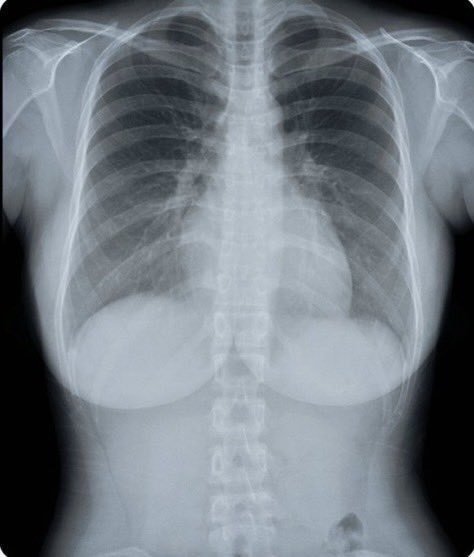

สาวสวยรายหนึ่งแชร์ภาพเอกซเรย์หน้าอกของตัวเองลงโซเชียล กลายเป็นกระแสฮือฮาในหมู่ชาวเน็ตโดยไม่คาดคิด ยอดเข้าชมพุ่งถึง 1.255 ล้านครั้ง หลายคนถึงกับคอมเมนต์ถล่มทลาย

ขณะเดียวกัน ก็มีบางคนแซวในมุมขำ ๆ ว่า “แบบนี้เรียกว่าโดนมองทะลุหมดแล้วล่ะ”, “ตรงล่าง ๆ ที่เป็นแผ่นขาว ๆ คืออะไร?” และ “เห็นชัดเลยว่ามีซิลิโคนอยู่สองก้อน”

จริง ๆ แล้ว การตรวจเอกซเรย์เต้านมหรือแมมโมแกรมสามารถช่วยตรวจหาจุดแคลเซียมหรือก้อนเนื้อในเต้านมได้ รวมถึงตรวจพบมะเร็งเต้านมระยะเริ่มต้นที่ยังไม่แสดงอาการ (ระยะศูนย์) ด้วยเหตุนี้ จึงมีการแนะนำให้ผู้หญิงที่เข้าเกณฑ์ ควรเข้ารับการตรวจคัดกรองเป็นประจำ เพื่อให้สามารถพบและรักษาได้ตั้งแต่ระยะเริ่มต้น